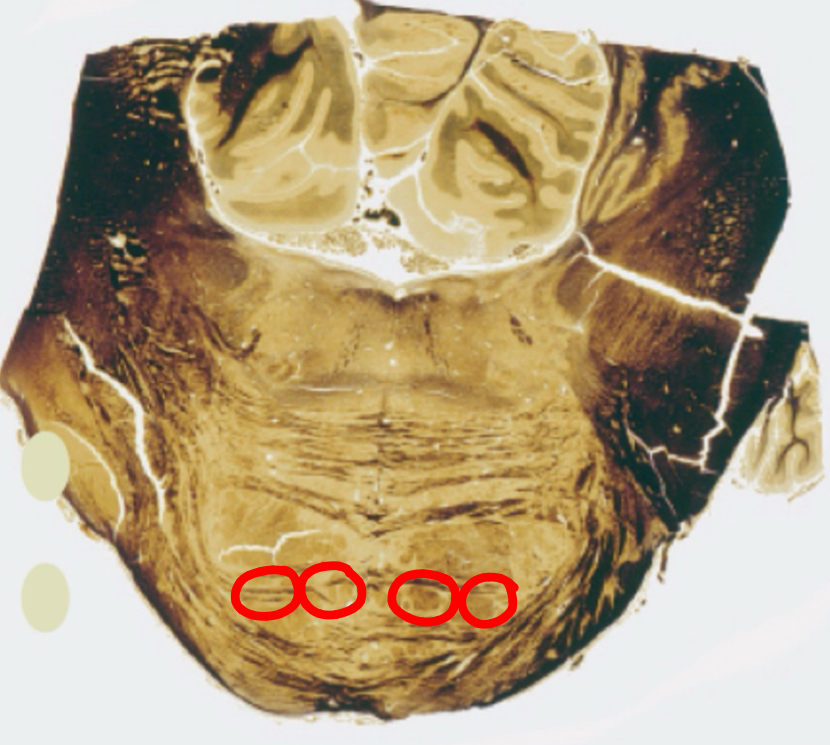

gracile tract caudal medulla II

gracile nucleus caudal medulla II

cuneate tract caudal medulla II

cuneate nucleus caudal medulla II

spinal tract of trigeminal caudal medulla II

trigeminal sensory nucleus

pyramids caudal medulla II